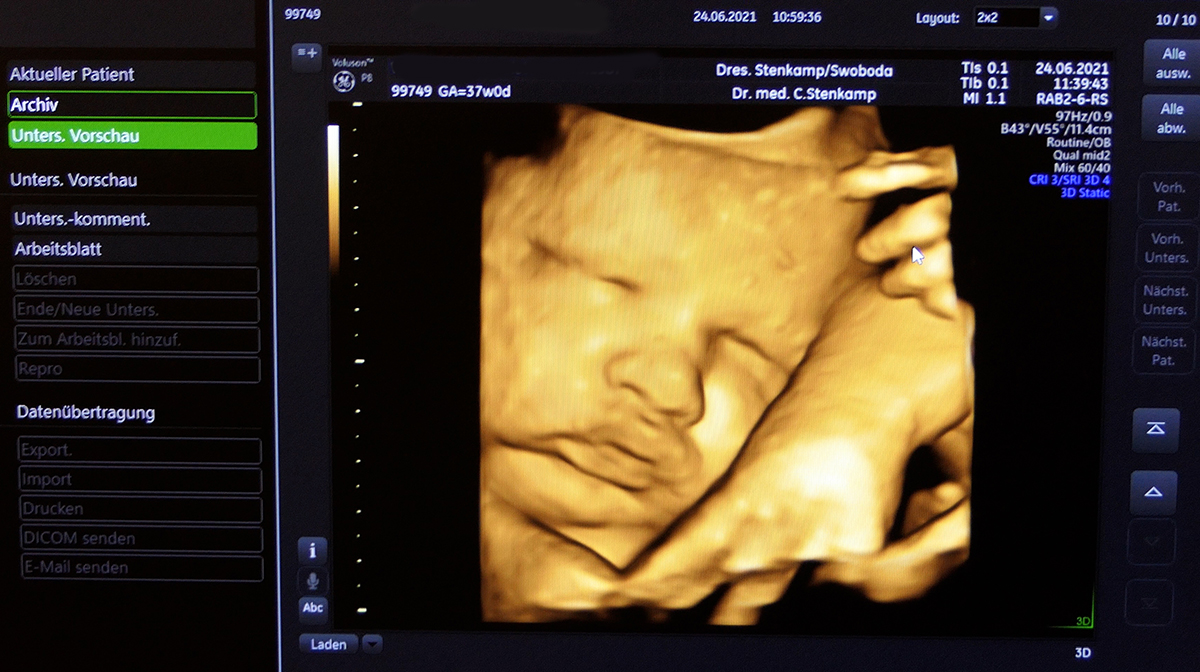

Anspruch auf gesetzlich geregelten Ultraschall

Gesetzlich hat jede Schwangere Anspruch auf drei Ultraschall -

Darüber hinaus bieten wir im Rahmen von IGEL (individuelle Gesundheitsleistungen auf privater Basis) noch folgende Unterschungen an:

Ultraschall -

Schwangerschaftsultraschall für den werdenden Papa

Untersuchung außerhalb der regulären Vorsorgetermine;

auch am Wochenende

Bei allen Ultraschall -